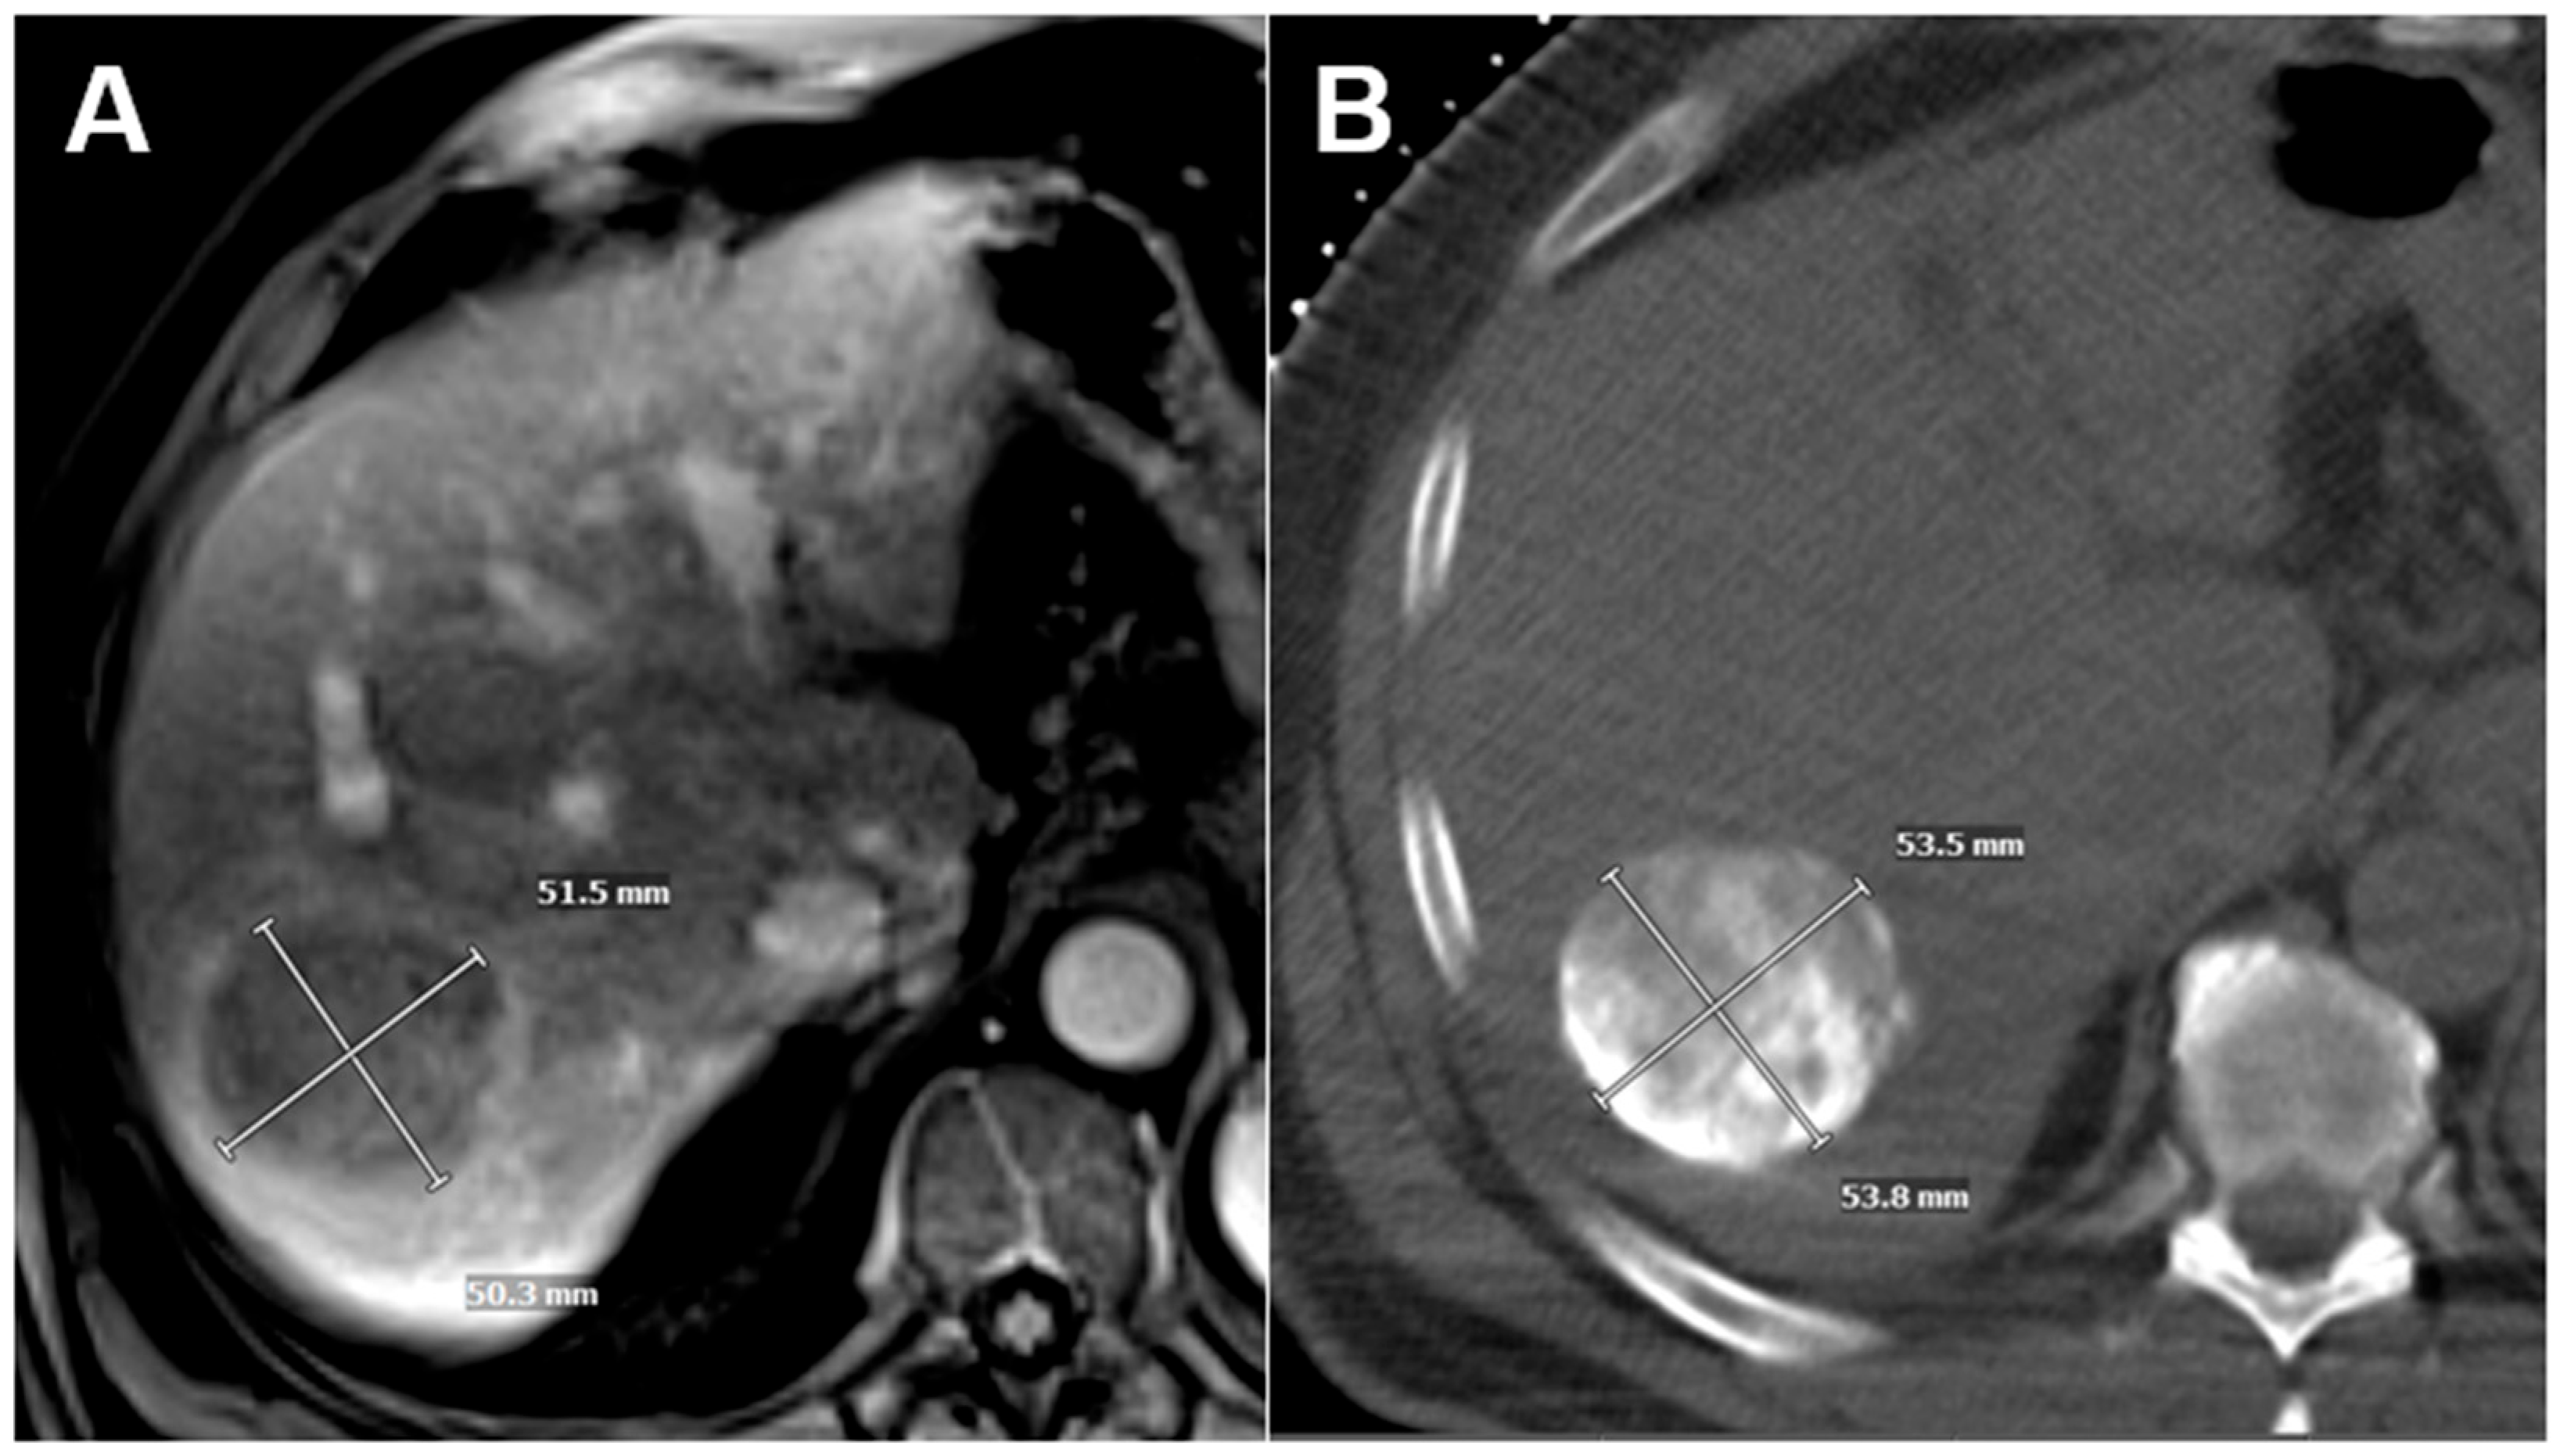

| Size of index tumor, mm (median, IQR) | 52 (33–72) | 52 (37–72) | 52 (31–71) | 0.45 |